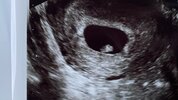

Niestety niezbyt optymistycznieWidać pęcherzyk bez zarodka, wielkość na 4 tydzień i 5 dzień, co jest absolutnie niemożliwe, bo do owulacji musiałoby dojść na tydzień przed datą spodziewanej @, a plemnik musiałby "czekać " na owu przez jakieś 6 dni... Pani doktor nie była zbyt optymistyczna niestety

Nie pamiętam co dokładnie mówiła, ale coś w tym stylu, że coś tam widać i że z tego pewnie będzie się tworzył zarodek. Jakaś plamka czy coś w tym stylu. Zarodek nie został uwidoczniony. Za tydzień mamy powtórzyć usg